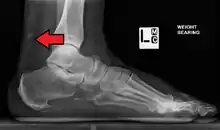

Magnetic resonance imaging may be useful to guide muscle biopsy and to investigate involvement of internal organs;[11] X-ray may be used to investigate joint involvement and calcifications.[12]